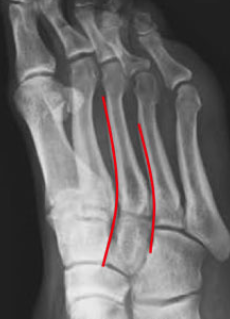

A(LEFT) shows the AP view.